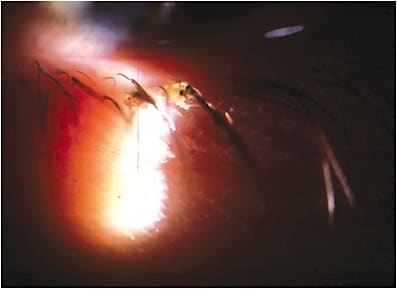

- Slit lamp. Start with the lids and lashes, looking for signs of blepharitis, especially if the patient’s symptoms or physical appearance are consistent with the diagnosis. Also, inspect the meibomian gland orifices and the line of Marx at the muco-cutaneous junction, as incomplete blinking can result in significant buildup of epithelial and other debris, including bacterial biofilm, which can block the glands. In addition, look at surface elements of the gland structure, including possible atrophy, evidenced by notching, inspissation and lid surface inflammation. These findings suggest MGD and, therefore, require further investigation.

Finally, inspect the conjunctiva — both bulbar and palpebral, directly and via transillumination, to assess gland structure. If you have one, use a slit lamp camera to transform it from an important diagnostic tool to a communication platform for patients. - Gland expression. I assess meibomian gland function by applying light fingertip pressure to the lid margin to simulate the force of a blink. Normal glands produce clear meibum with light pressure. Alternatively, you may use commercially available tools to assist in expression. Abnormal secretions (e.g. turbid, thick meibum) can be noted during this exam segment.